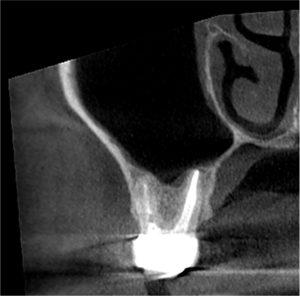

言葉で書くのは簡単ですが、これには非常に時間がかかりとても困難な治療でした。そこにMTAセメントを用い、根の先端の方(赤矢印)と吸収部(黄色矢印)を同時に埋めました。

黄色矢印の左の方を見ていただくとわかると思いますが、外にはみ出しているのがわかるかと思います。

これはMTAセメントを押し込んで、わざとはみ出しています。

この後歯茎を開いて、はみ出したMTAセメントと除去しきれていない外部吸収部を除去して、グラスアイオノマーというセメントにより同部を埋めました(赤矢印)。

これも言葉にして書くと簡単なのですが、これをピッタリ埋めるのが非常に難しかったです。